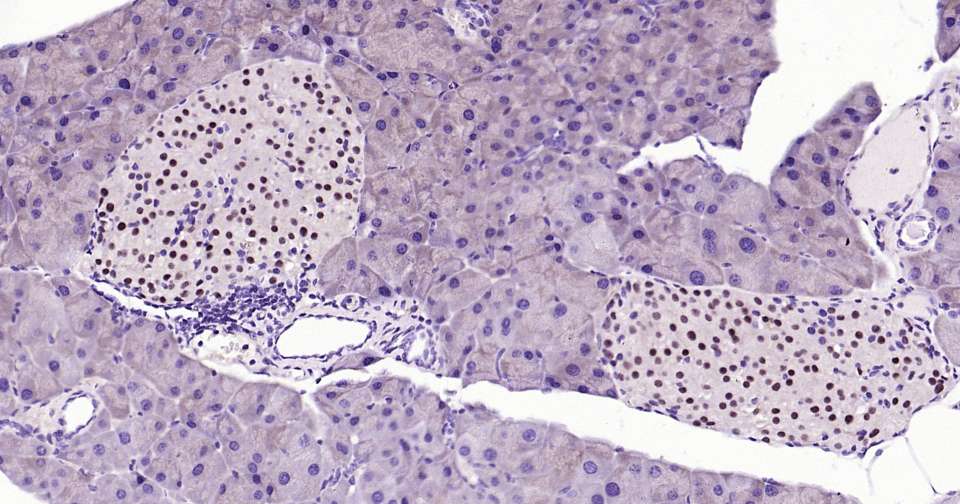

Immunohistochemical analysis of paraffin embedded mouse pancreas tissue slide using IHC0367M (Mouse PAX6 Kit).